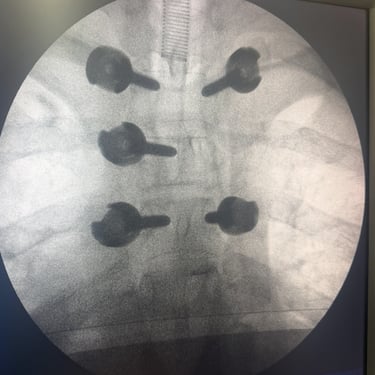

Tumor vertebral dorsal hemorrágico: descompresión medular, biopsia y artrodesis dorsal

El tumor vertebral dorsal puede ocasionar compresión de la médula espinal, dolor intenso y alteraciones neurológicas progresivas. En algunos casos, estos tumores presentan componente hemorrágico que incrementa la presión sobre las estructuras nerviosas. El tratamiento quirúrgico puede incluir descompresión medular para liberar la médula espinal, toma de biopsia para establecer el diagnóstico histopatológico y artrodesis dorsal con instrumentación para estabilizar la columna vertebral. Este abordaje permite reducir el riesgo de daño neurológico, aliviar los síntomas y mantener la estabilidad vertebral. La cirugía se realiza con técnicas especializadas que buscan preservar la función neurológica y mejorar la calidad de vida del paciente.